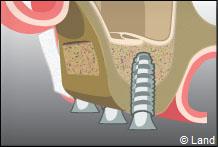

LES COMBLEMENTS SOUS-SINUSIENS

Ce comblement osseux est réalisé avant ou en même temps que la pose des implants.

L’intervention est réalisée sous anesthésie locale. Dans cet exemple le forage intéresse la paroi latérale du sinus.

Une fenêtre est délimitée et réclinée à l’intérieur du sinus de manière à aménager un espace. Cet espace est rempli par le matériau de comblement qui peut être recouvert par une membrane.

L’implant est posé dans la même séance ou 4 à 6 mois après la chirurgie de comblement.

Actuellement, tous les biomatériaux peuvent être utilisés pour les comblements sinusiens.

Après le comblement, il n’a jamais été décrit une quelconque perturbation de la physiologie sinusienne.